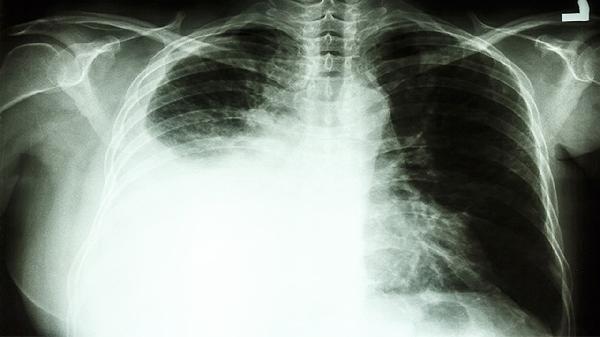

支气管肺癌的病因主要有吸烟、职业暴露、遗传因素等。支气管肺癌是起源于支气管黏膜或腺体的恶性肿瘤,其发生与多种因素相关。